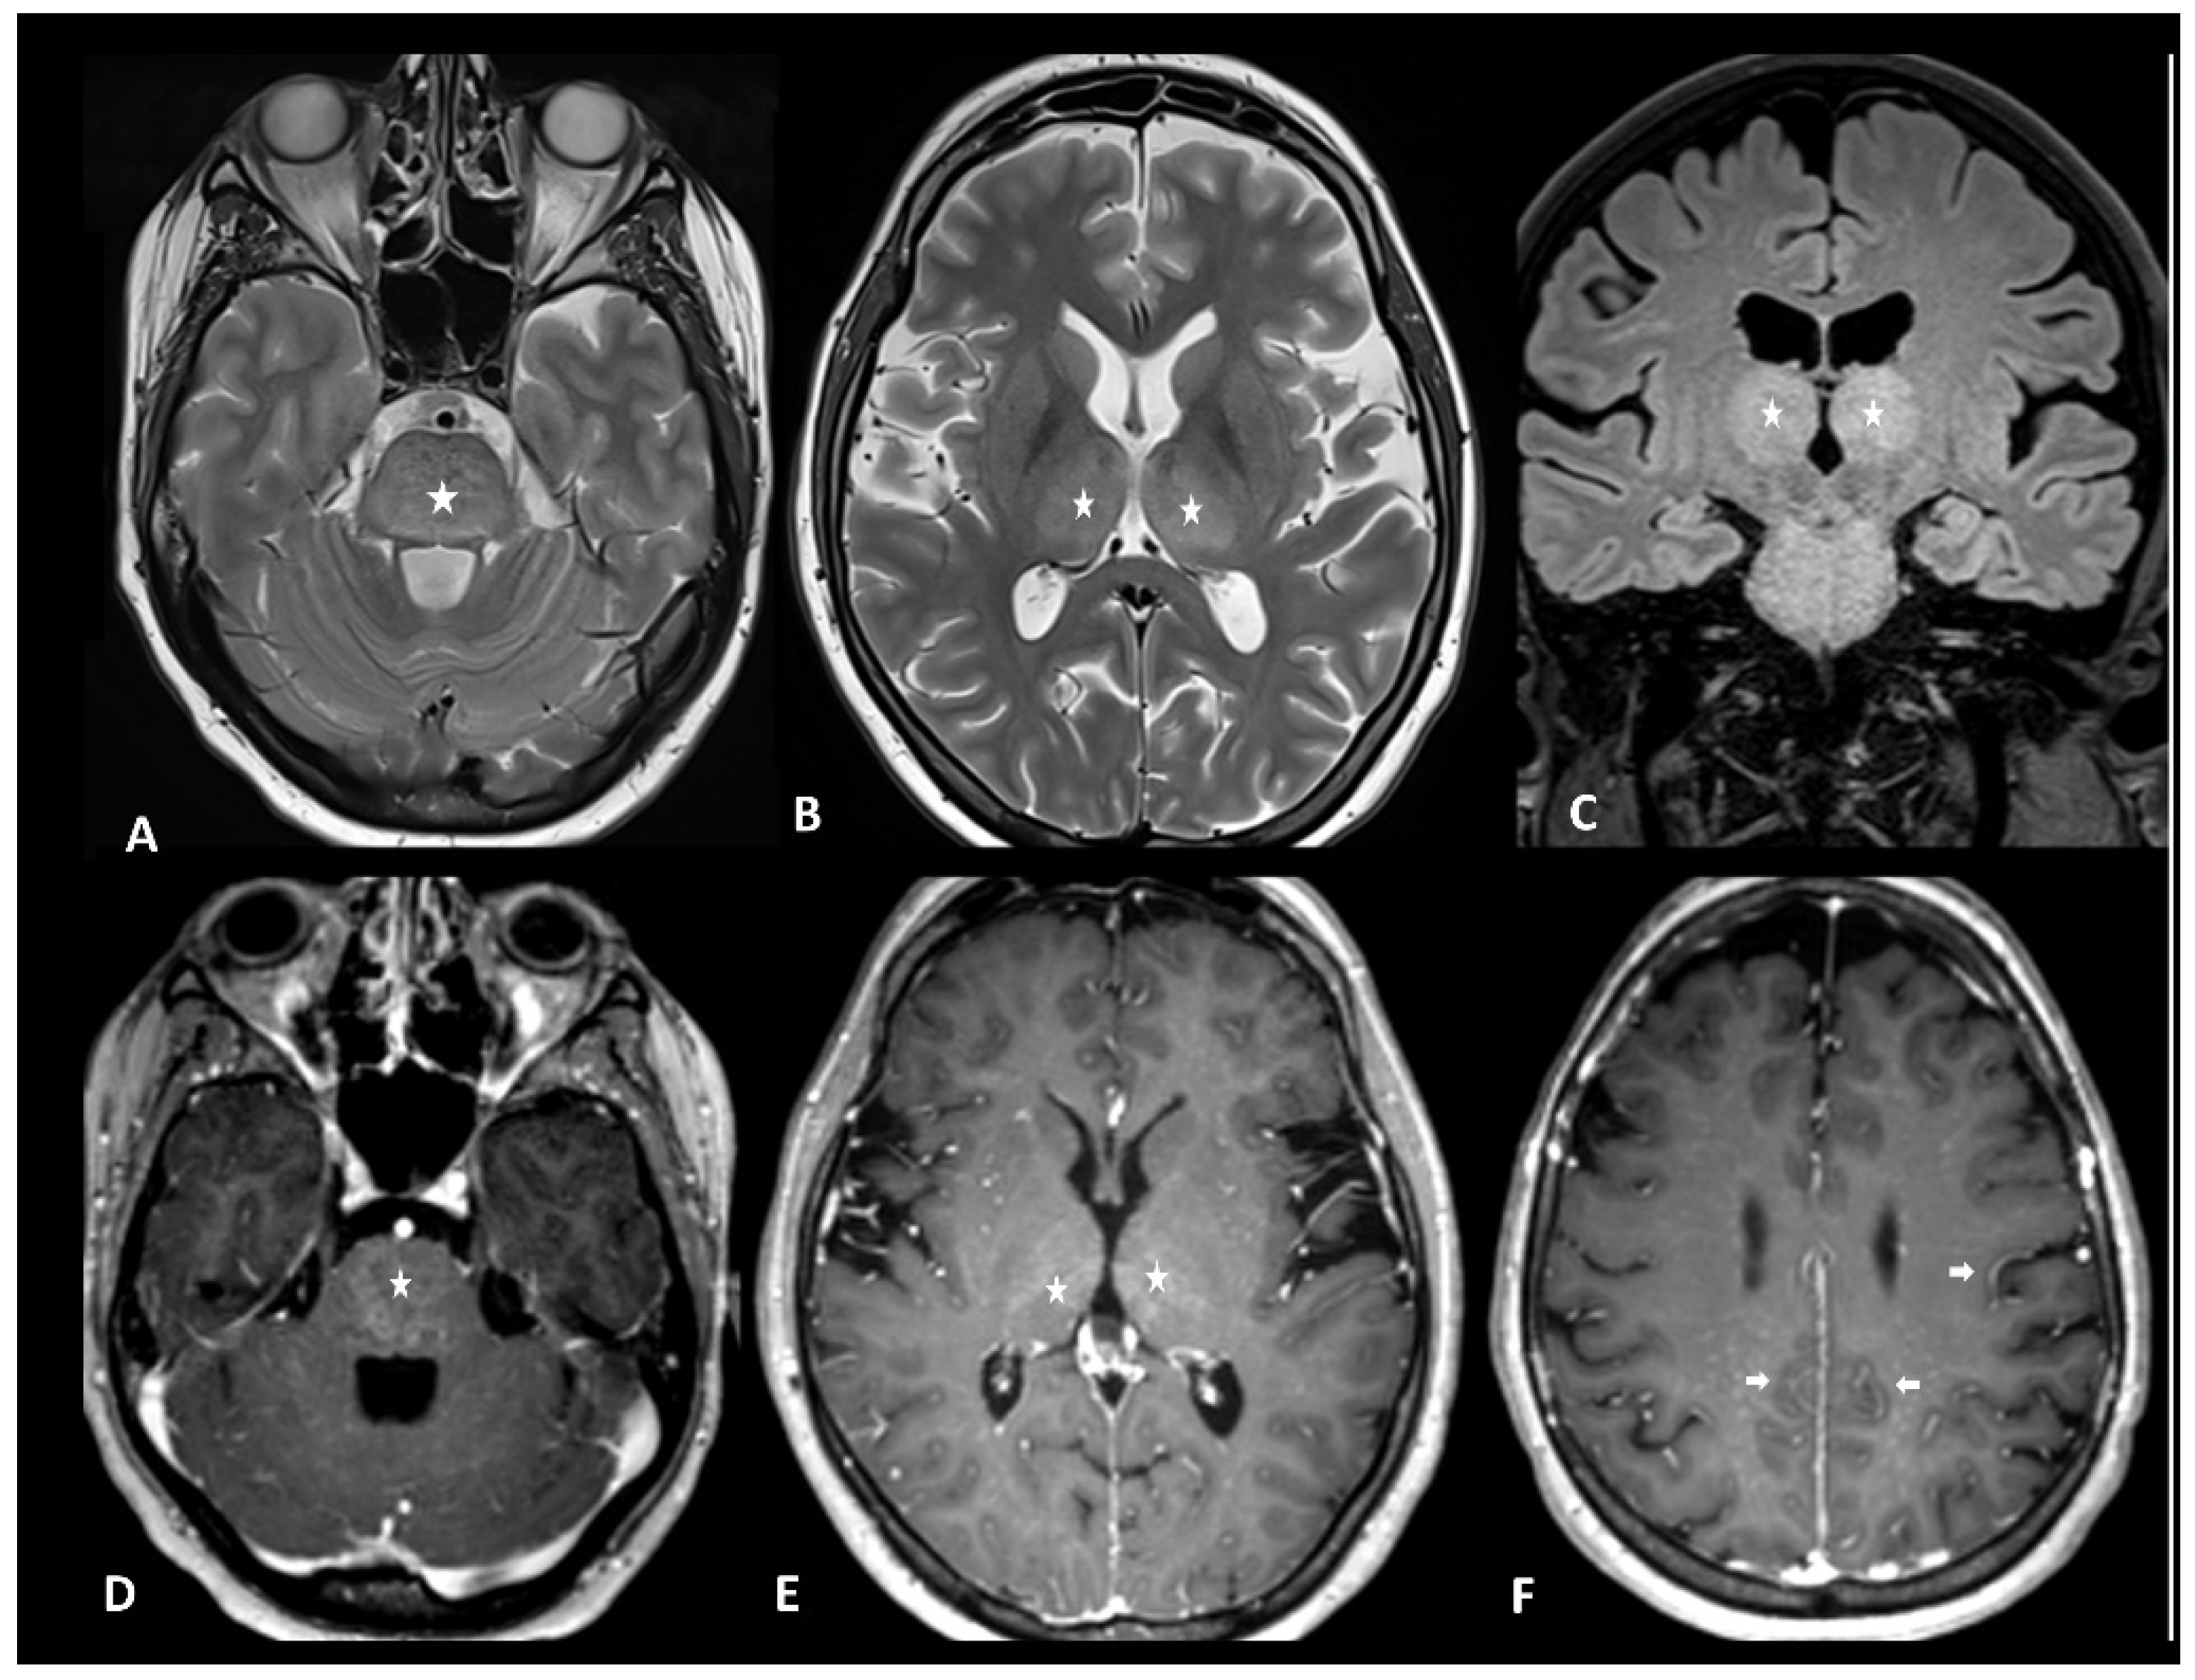

ICANS is the most common neurological immunotherapy adverse event, touching 23–67% and 40–62% of patients with lymphoma and leukemia, respectively, with severe events reported in 12–30% and 13–42% of patients with lymphoma and leukemia, respectively [106]. Clinical presentation is wide, including encephalopathy/delirium, aphasia, depressed level of consciousness, seizure, headache, tremor/myoclonus, motor dysfunction, dysarthria, neuropathy, meningismus, hemiparesis, and hallucinations [107]. The diagnostic workup usually includes lumbar puncture, contrast-enhanced brain MRI, and EEG. Because coagulopathy can occur with severe ICANS, serologic testing for coagulopathy may also be included.

Neuroimaging is unremarkable in most cases but can show T2 and FLAIR hyperintensity (especially bilateral thalami and brainstem), vasogenic edema, leptomeningeal enhancement, multifocal microhemorrhages, cortical diffusion restriction, and transient corpus callosum lesions [108] (Figure 13). Diagnostic workup with radiological clues and main differential diagnoses are reported in Table 4.

Figure 13.

Immune effector cell-associated neurotoxicity syndrome in a 28-year-old female patient suffering from diffuse large B-cell lymphoma. The patient was admitted for CAR T infusion in the context of disease progression. Twenty-four hours after the first infusion, the patient developed fever, tachycardia, dysphagia, and dyskinesia. MRI revealed bithalamic and brain stem hyperintensities (asterisks) on T2 and FLAIR (A–C) and contrast enhancement (D,E). Diffused perivascular spaces enhancement (arrows) was also observed (F). No sign of infection was found during biological tests. Despite intravenous methylprednisolone infusion, the patient died 5 days later.